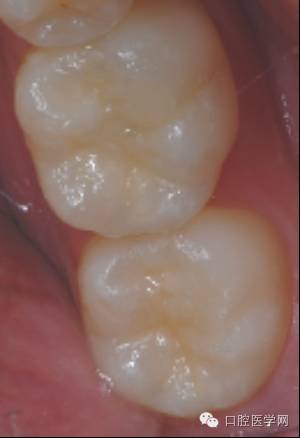

前后对比

术前

术后

小结:

1 对于一部分牙合面形态完整的病例,印章法是很好的充填方式,临床上有较多的适应范围。

2 树脂充填无论比色,备洞,隔湿 抛光,各方面的细节都非常重要,只有每一步都做好了才可能做出优秀的病例。